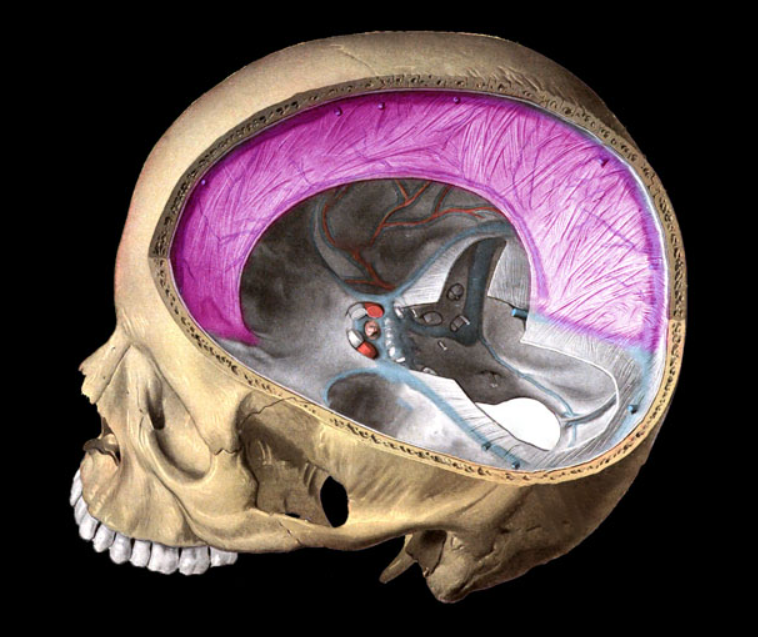

falx cerebri

falx cerebelli

tentorium cerebelli

dural sinus

vertebral arteries

Basilar artery

internal carotid arteries

Arterial circle